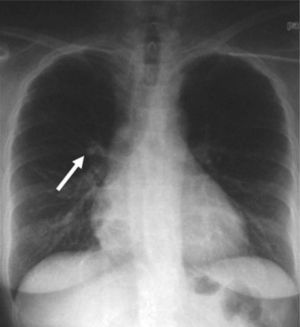

La paciente fue intervenida quirúrgicamente mediante cirugía transesfenoidal. El informe de anatomía patológica de la pieza fue de hipófisis normal. En la primera revisión tras la cirugía persistía la clínica y la bioquímica de hipercortisolismo. El informe de la radiografía de tórax de la consulta preanestésica describía una imagen de aspecto seudonodular en probable relación con falsa imagen secundaria a superposición de estructuras óseas y vasculares. En la radiografía de control persistía la imagen nodular de menos de 1 cm (fig. 1), que se confirma en la tomografía computarizada (TC) torácica, y se describía como un nódulo sólido de 11,6 × 16 mm en el lóbulo medio (fig. 2).